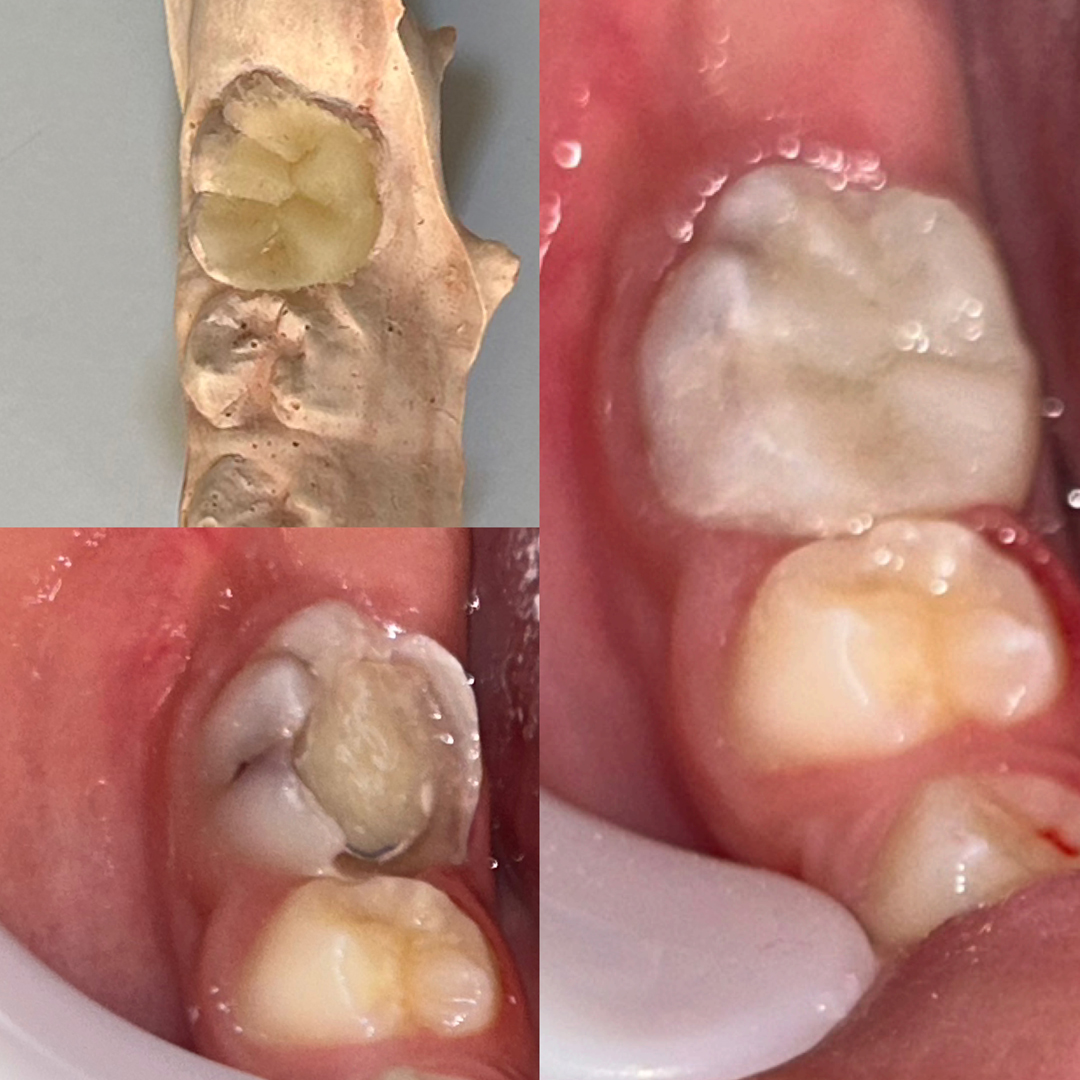

Dr. Diego Gomes é cirurgião-dentista graduado pelo centro universitário cesmac, especialista em Endodontia (ABO-Recife) e pós-graduado em Prótese Fixa, com atuação voltada para o alívio da dor, a preservação dos dentes e o cuidado integral do paciente.

Seu trabalho é baseado em diagnóstico clínico e radiográfico criterioso, uso de tecnologia e atenção individualizada. Com uma abordagem técnica precisa e humanizada, realiza o tratamento completo, incluindo procedimentos preventivos, tratamento de canal e a reabilitação do dente, permitindo que ele volte à sua função por meio de restauração em resina composta ou coroa em cerâmica e, quando necessário, pino de fibra de vidro, sempre com foco na qualidade de vida e no bem-estar.